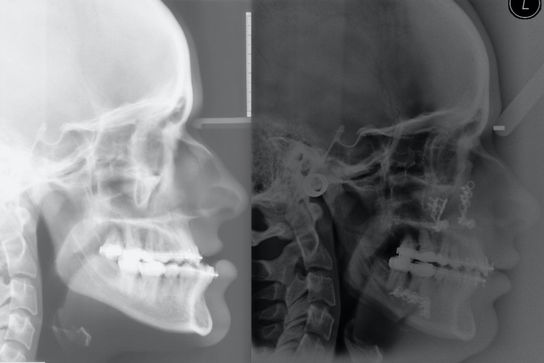

Jaw Surgery / Orthognathics

Jaw disproportion can have profound affects on chewing, appearance and self confidence. Rhodri works with his surgical colleague Kevin McMillan and with a team of specialist orthodontists to manage these challenging and sensitive problems.